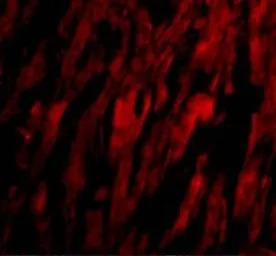

IHC-P analysis of human heart tissue using GTX85073 BAP29 antibody.

Working concentration : 10 μg/ml